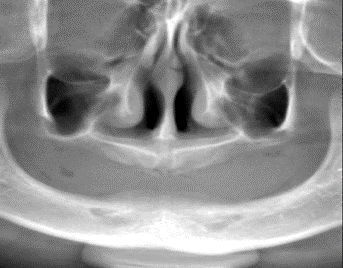

患儿上下颌牙列缺失、牙槽嵴低平明显